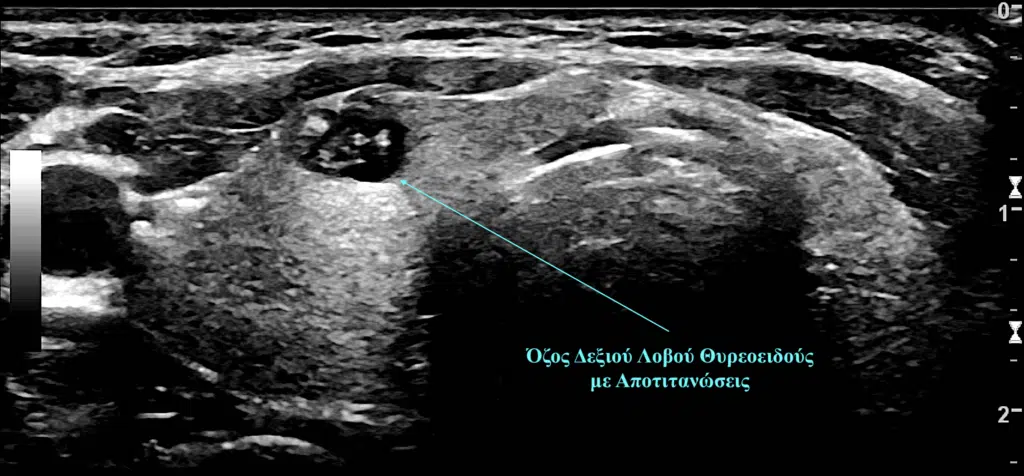

Η απάντηση στο ερώτημα “πότε οι όζοι θυρεοειδούς είναι επικίνδυνοι” προέρχεται από τα υπερηχογραφικά χαρακτηριστικά ενός όζου, καθώς κάθε επικίνδυνος όζος του θυρεοειδούς εμφανίζει και ύποπτα χαρακτηριστικά στο υπερηχογράφημα. Εικόνα από γυναίκα ασθενή μας με επικίνδυνο όζο στο δεξιό λοβό του θυρεοειδούς αδένα που έφερε αποτιτανώσεις, η παρακέντηση του οποίου ανέδειξε την παρουσία θηλώδους καρκίνου του θυρεοειδούς αδένα.